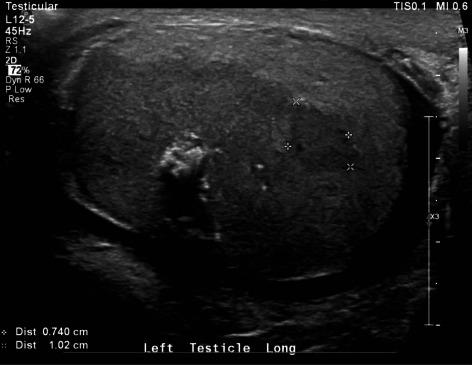

We report a case of esophageal cancer with solitary metastasis to the testicle in a 71-year-old man. The tumor was picked up on physical exam following new onset complaints of pain and swelling. While most testicular masses in older men are due to lymphoma, this case highlights the need to consider metastatic disease as a source of new symptoms in patients with a recent cancer diagnosis.